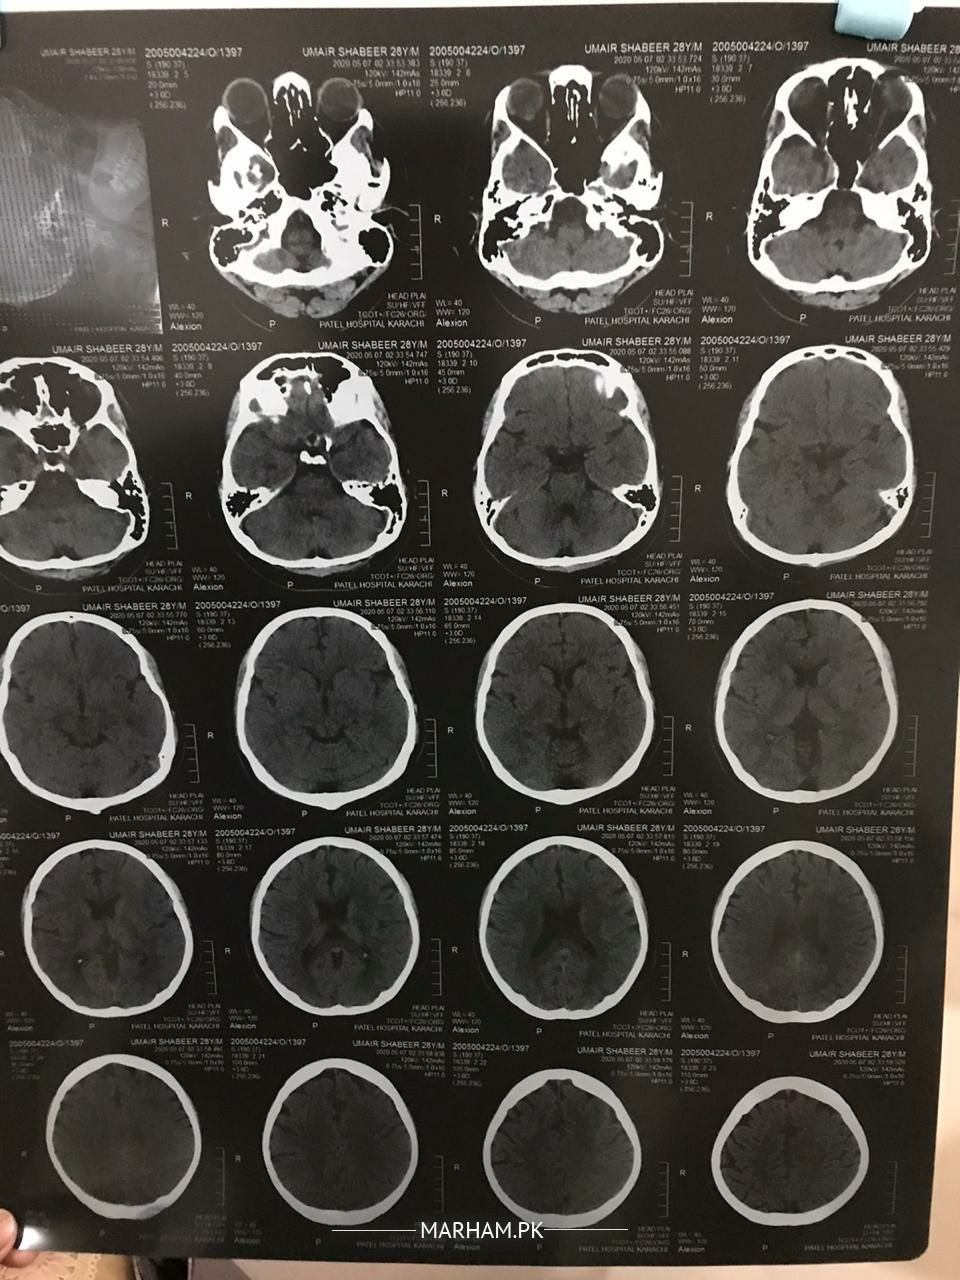

Since past 2 days, I was having constant vertigo, head movement making it worse. Cannot sit or walk, did epley's maneuver but didn't work. Also my left eye is getting a bit blurry. No problems in hearing at all. I'm seeing little black & white dots sometimes in vision. Condition is getting better but I'm worried if its some serious condition that requires MRI. Blood reports and CT scan are attached. Taking serc 16mg twice with modilium. Please help, thanks.

Better to consult with qualified  neurologist . And let him decide either go through MRI or not?? Mean while serc 16mg tid. Stugran forte bid.

Attach Photo here: